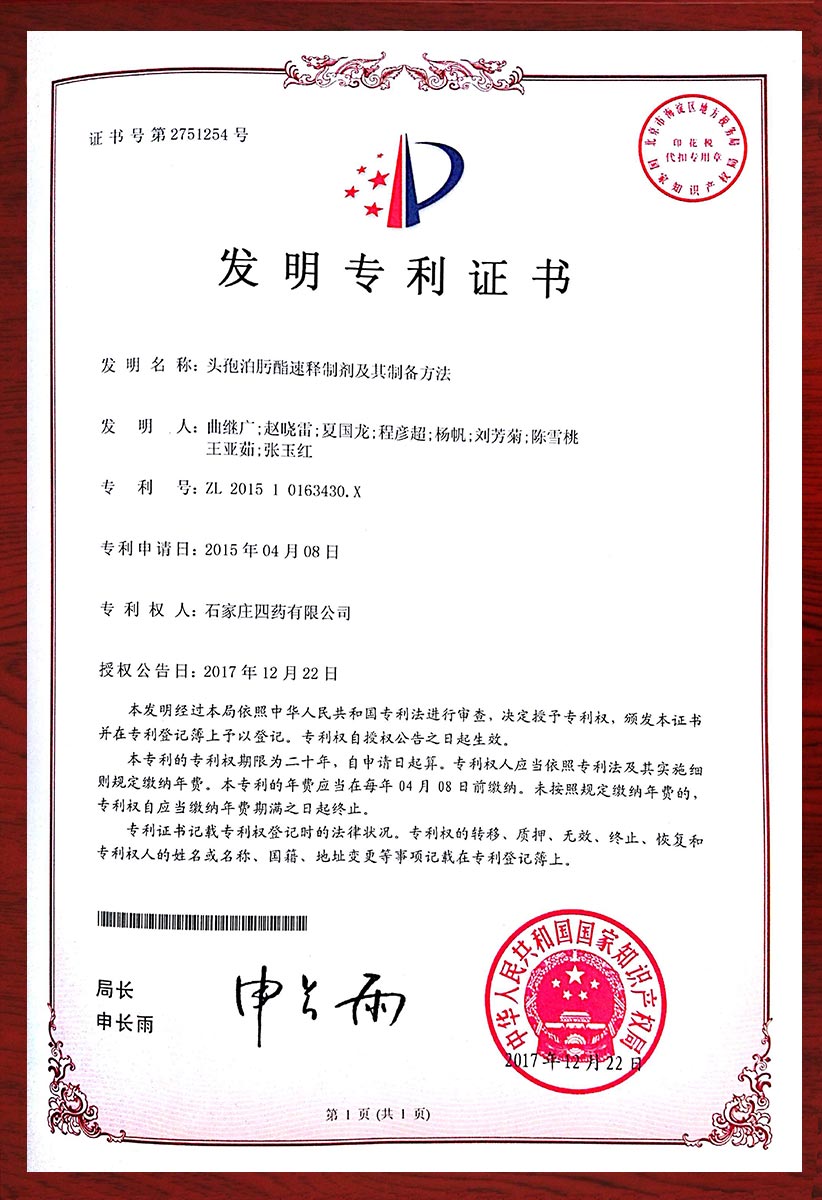

专利证书